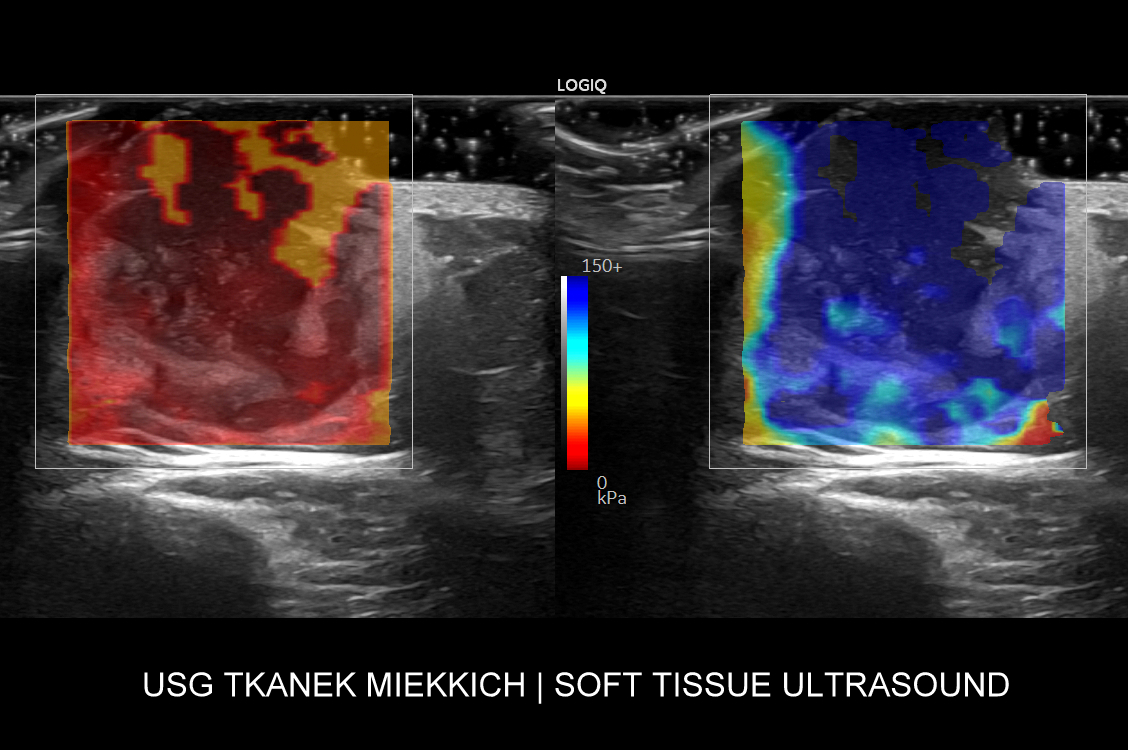

Najistotniejszą grupą chorób tkanek miękkich są nowotwory złośliwe wywodzące się z tkanki łącznej, czyli mięsaki. Występują one częściej młodych i zdrowych dotąd dorosłych, częściej u kobiet, a objawiają się zwykle w sposób podobny do łagodnych schorzeń takich jak przepukliny, czy tłuszczaki. Badanie USG pozwala na szybie rozpoznanie mięsaka i wdrożenie szybkiej ścieżki leczenia.

Aparatura do USG skóry

Pracownia dr Tomasza Szczepańskiego świadcząca usługę USG skóry we Wrocławiu, jako jedna z kilku w Polsce, wyposażona jest w aparaturę dysponującą zaawansowaną technologią, oprogramowaniem oraz specjalistycznymi sondami umożliwiającymi obrazowanie skóry o niestandardowo wysokiej rozdzielczości, a także diagnostykę funkcjonalną i biologiczną zmian chorobowych w skórze oraz w powłokach ciała.